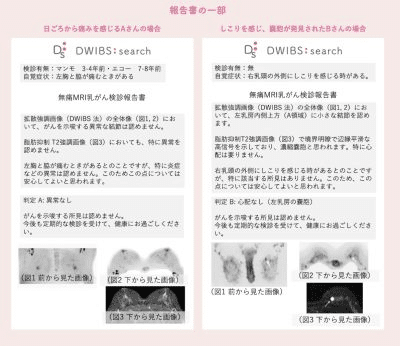

ドゥイブス法を用いた検査の陽性的中率(PPV)は現在20%程度です。厚生労働省が指標としてマンモグラフィに課している基準はPPV2.5%以上であることを考えると、従来検査の数値を遥かに超える成績だとわかってもらえると思います。

価格は2万円程度と、他の検査に比べると高いと思われるかもしれません。でも、検査をした方には詳細な検査レポート「乳房マップ」をお渡ししています。これを見て、ご自分の乳房の状態をしっかり把握していただくことができます。

——「乳房マップ」いいですね。自分に乳がんのリスクがどのくらいあるのか把握できるのはとても嬉しいです。リスクが低そうなら、その後は2年に1度の検診を受ける、リスクが高いようなら、毎年検診を受けるなど、今後の検診予定も立てられそうです。

それでも開発した自分はこの技術が優れていることを知っていましたし、自分自身だけが分かる精度の高め方、精度の保持のしかたがありましたから、批判されても勇気を持って進めていきました。その結果、PPV(陽性反応適中度)約20%という、従来の検診を遥かに超える成績を、乳腺外科の先生が次々に発表してくださり、手応えを感じています。